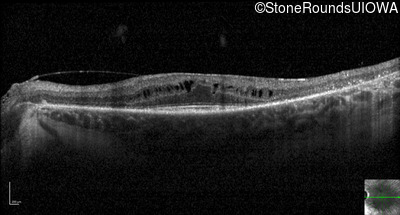

Optical Coherence Tomography - Left - 20/30

Exemplar / OCT Stack

OCT Stack